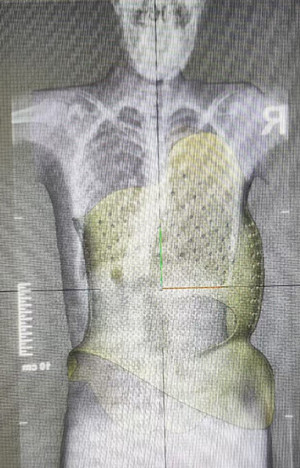

孩子在生长发育阶段,身高与体重随时都会发生变化。尤其在生长发育高峰期时,身高会增长很快。脊柱侧弯支具有抗弯度的力,也有抗旋转的力,材料是硬性的,所以孩子刚开始穿,压力会感觉明显,甚至有不适感,建议要有1周一两周的适应期,可由松到紧,时间由短到长,适应后再达到要求的穿戴时间和紧度。而脊柱也会跟随产生弹性变化,逐渐适应压力,产生向好的方向上的变形。所以我们也要定期检查,了解评估变化程度,做压力的的增减调整,最大程度的去减小侧弯度数及旋转度数。一般支具复查时间建议是3一6个月复查做一次,2一4岁的孩子2个月复查一次。

每次复查都要测量身高体重,了解穿戴支具前后数据。对支具做出适当调整,如果身高增长超过4cm以上,支具有可能需要更换了。体重如果变化太大,也要更换支具。原因是胸廓围度出现了增长的变化,压力点位置改变了。